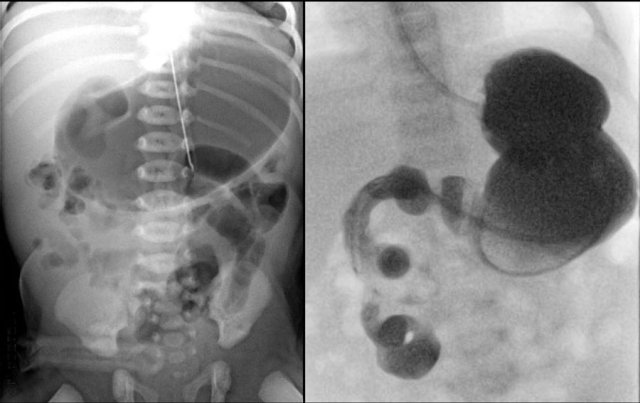

Radiographs will show multiple dilated bowel loops and absence of air in the colon as seen on the image on the left.

A colon enema will show a microcolon with contrast filling ending blind in the ileum (arrow on image on the right).